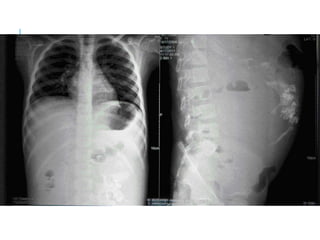

ABDOMINAL X-

RAY

AP

PA

GAS UNDER DIAPHRAGM